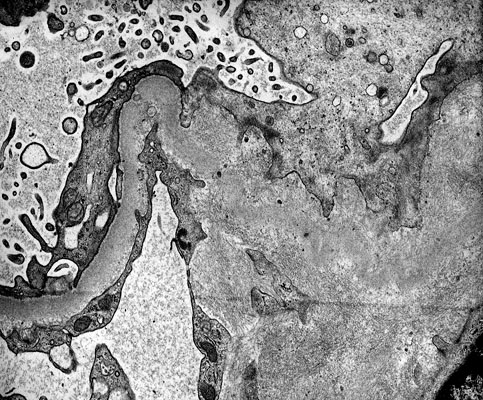

Amyloidosis, EM

Amyloid fibrils can be seen in deposits (arrow).